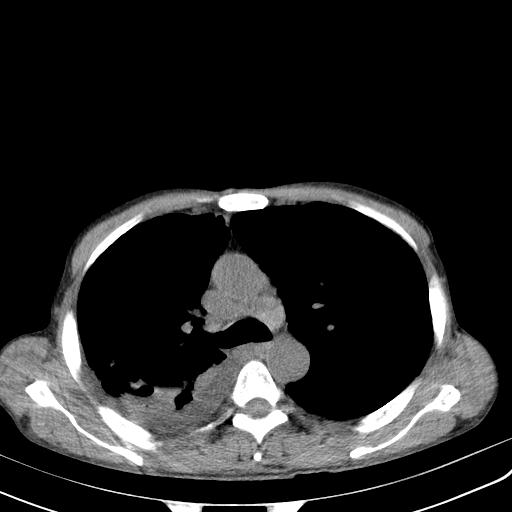

男性 75  咳嗽 一周前发热最高达39

右肺继发型tb并右侧tb性胸腔炎,右侧胸腔大量积液并右下肺膨胀不全,慢支肺气肿、多发肺大泡。建议抽胸水实验室检查并复查排除恶性在占位。

右上肺继发型肺结核,右胸腔中等量积液。

左上肺大泡。

结核的基础上有纵隔淋巴结肿大,右侧有胸水,但右侧纵隔反而窄,说明有肺有不张。

再就是右下肺有块影,和不张混合,还是不能除外肺癌。

补充材料,患者2月份ct片大致正常,双侧胸腔积液,2月份抽胸水未发现ca细胞,现患者发热,痰多,各气管通畅,

1)右肺继发型肺结核。2)左肺胸膜下多发性肺大泡。3)右侧胸腔积液。